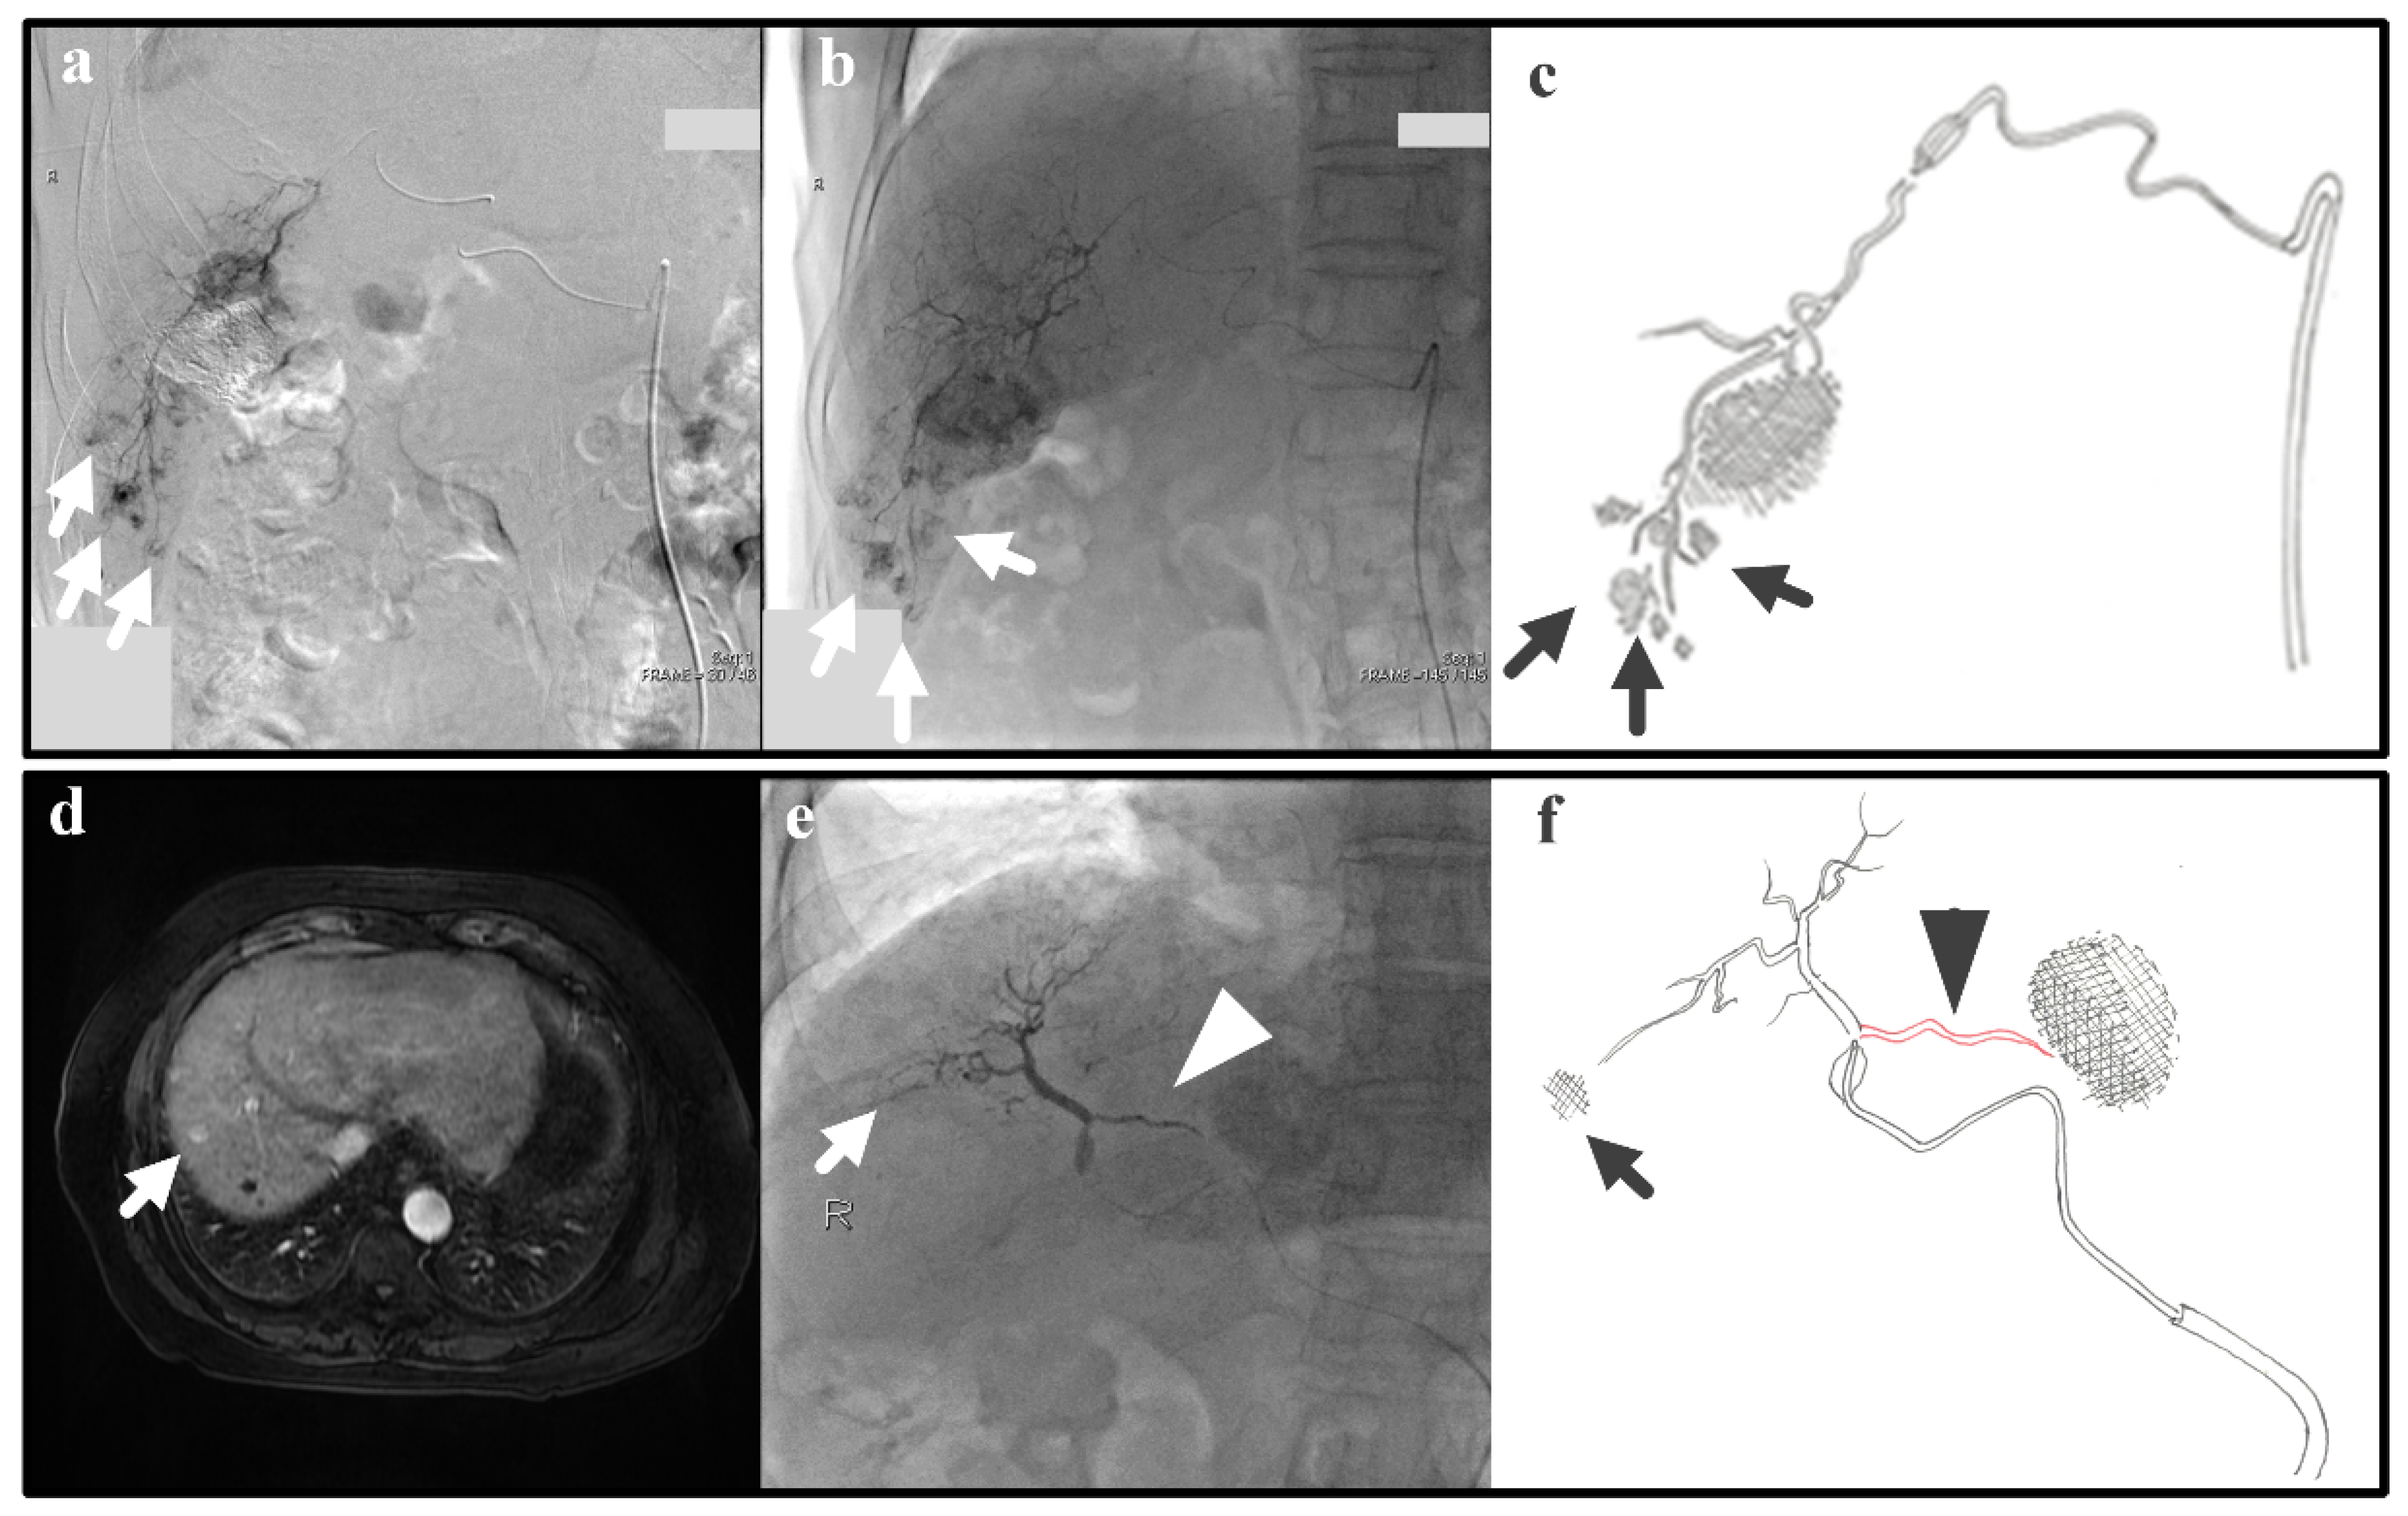

In real clinical cases, arterial hemodynamics is complex due to varied and not-always-visible collateral pathways. Thus, we examine real cases that are relevant to the IVM testing; despite the simplicity of the IVM, the successfulness/unsuccessfulness of clinical cases can also be explained with the IVM. The following two clinical cases represent Experiments 1 and 2, which give as a result efficient and inefficient B-TACE procedures, respectively. Experiment 1 (i.e., a single tumor and successful B-TACE) is similar to the case of a patient (patient 1) with previous embolization of a 3-cm tumor in S6 that underwent B-TACE after multiple early stains were detected in angiogram (arrows in Figure 8a). Dense accumulation of lipiodol with miriplatin was shown during B-TACE (arrow in Figure 8b,c).

Experiment 2 (i.e., a single tumor and unsuccessful B-TACE) is similar to the case of a patient (patient 2) that underwent B-TACE after an early 1-cm tumor at S8 (i.e., the therapeutic target) was detected with MRI (Figure 8d). During embolization of S8, the microballoon tip pressure was above 64 mmHg, suggesting that collateral circulation existed. Indeed, accumulation of lipiodol with miriplatin was not enhanced (arrow in Figure 8e,f) as a pronounced collateral pathway emerged toward S4 (arrowhead in Figure 8e,f). These two clinical cases show that the IVM can reproduce clinically realistic scenarios.

Figure 8. Patient 1: (a) Angiogram for tumor detection, (b) lipiodol accumulation during B-TACE, (c) a hand drawing showing the tumors, the hepatic artery, and the microballoon catheter. Patient 2: (d) MRI for tumor detection and (e) no lipiodol accumulation in the tumor (arrow), collateral pathway promotion (arrowhead) during B-TACE, and (f) a hand drawing showing the target tumors, the hepatic artery, the microballoon catheter, and the collateral artery.